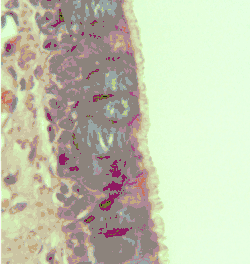

Additional images

-

Cross-section of pseudostratified columnar epithelium -

Second cross-section